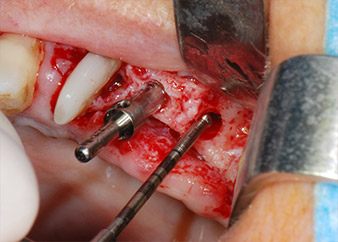

Prior to implant placement, infected tissue was removed from the alveolar bone in the implant site and around the abutment teeth with an insert originally designed for bone shaping and collecting bone chips (Piezomed, insert B5) (Figs. 6 and 7).

Implant beds were prepared at sites 25 and 26 with rotary instruments, used in a contra-angle handpiece with a 20 : 1 transmission ratio with an updated powerful implant motor (Implantmed, W&H) (Fig. 8).

The final preparation next to the sinus was again carried out with a piezoelectric instrument (Piezomed, insert S2).